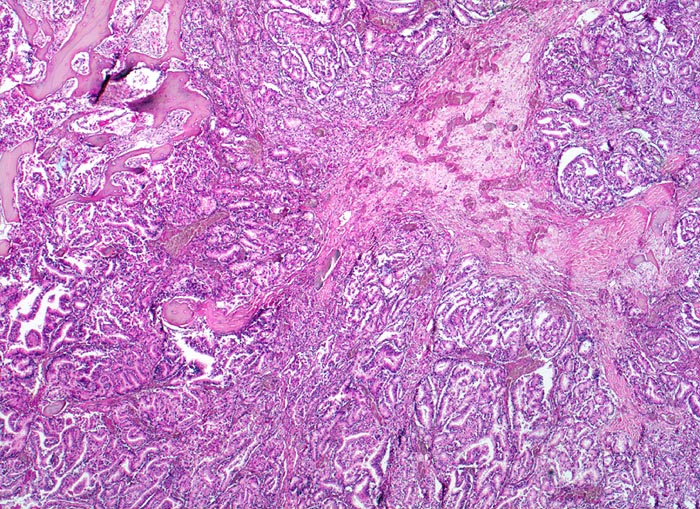

Prostatakarzinom: Knochenmetastase

Grösseres Infiltrat eines Adenokarzinoms mit dos à dos liegenden Drüsenschläuchen. Areal mit Granulationsgewebe und kleinen Knochenresten.

Bei Autopsie finden sich zahlreiche, teils osteoplastische, teils osteolytische Metastasen im Bereich der Wirbelsäule. Die Karzinomdrüsen sind immunhistochemisch positiv für Prostata spezifisches Antigen.

Bekanntes metastasierendes Prostatakarzinom. St.n. bilateraler Orchiektomie. Diffuse Schmerzen im Bereich der Wirbelsäule. Der Patient verstirbt an einem Myokardinfarkt.